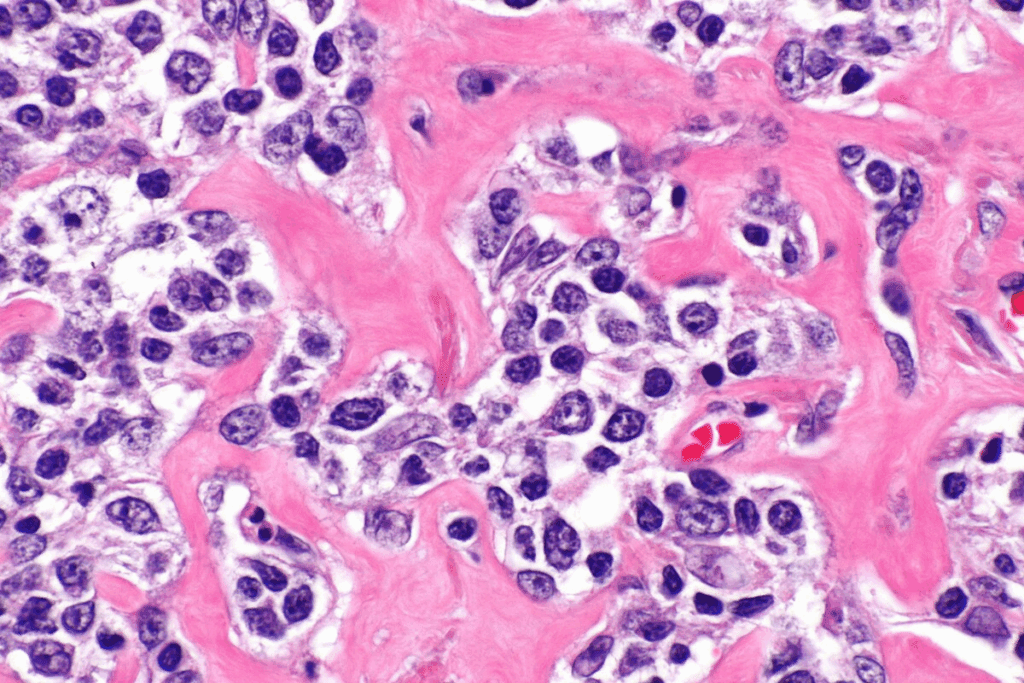

Lymph Node Biopsy: The Gold Standard

A lymph node biopsy is key for diagnosing lymphoma. It involves taking out a lymph node or part of it for a microscope check. This lets pathologists see if lymphoma cells are there.

A medical expert says, “Lymph node biopsy is essential for diagnosing lymphoma. It shows the tissue structure and cell details needed for accurate diagnosis and subtyping.”

Diagnosing lymphoma is complex. It needs a mix of clinical evaluation, imaging studies, and looking at lymphoid tissues under a microscope.